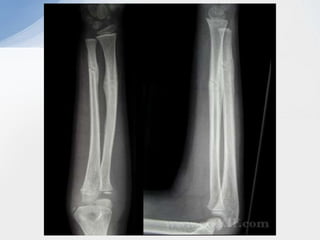

‘Both Bone’ Fractures

Types • Location –proximal, middle or distal • Characteristics – displacement, angulation and rotation • Plastic deformation • Incomplete – Buckle or torus fractures – Greenstick fractures • Complete • Monteggia • Both bone • Galeazzi